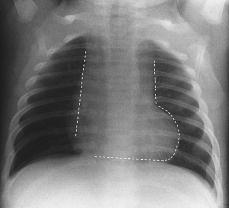

诊断:○ 靴型心○ 梨形心○ 普大型心脏○ 正常心脏○ 以上均不是病史

2)"主动脉"型:左心缘向外膨凸,心腰凹陷,主动脉结凸出,形如靴形.

天天师兄说明:靴型心:心脏形状像靴子一样,特点就是心腰明显凹陷,左

60主动脉型靴形心左心室扩大法洛四联征,主动脉瓣膜疾病,高血压心脏病